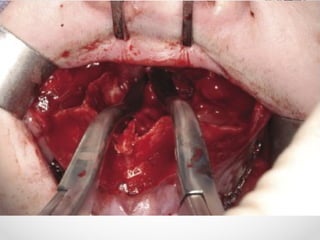

Internal Fixation

• Bone plates should be placed through intra-oral route wherever

possible

• External incisions are used for lower border of mandible & condylar

neck; also preferred in grossly resorbed edentulous mandible

• In simple mandibular #, mono-cortical 2mm plates provide

adequate fixation

• In ant mandible 2 plates are used while posteriorly one plate is

sufficient

• In complicated # with gross comminution, tissue loss, infection a

load bearing osteosynthesis with rigid internal fixation & bicortical

screws are required

• Management of condylar # is controversial

• Bilat displaced condylar neck # & high intracapsular

# have poor outcome and are better managed by

Open reduction